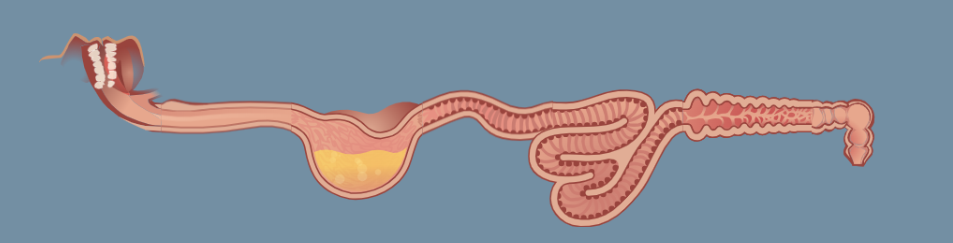

order of digestive pathway

mouth/pharynx, esophagus, stomach, small intestine (duodenum), small intestine (jejunum, ileum), large intestine, rectum